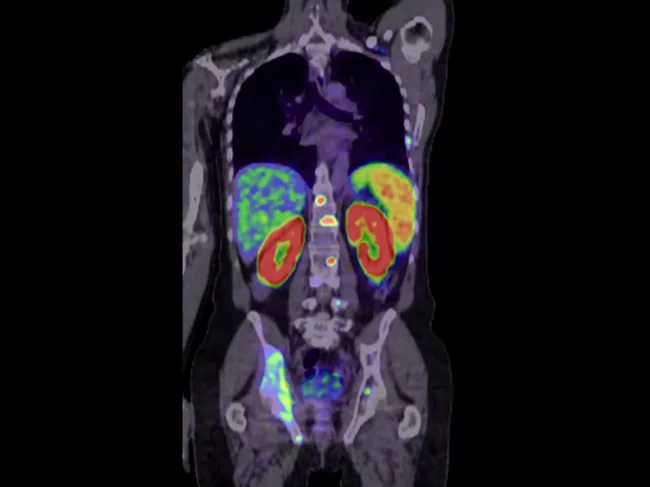

PET image of torso

FDA approves Telix’s radiopharmaceutical prostate cancer imaging agent Illuccix

PERTH, Australia – The FDA has given the green light to Telix Pharmaceuticals Ltd.’s lead radiopharmaceutical imaging agent, Illuccix, for prostate cancer. Illuccix is a kit for the preparation of gallium-68 (68Ga) prostate-specific membrane antigen (PSMA) 11 for imaging prostate cancer with positron emission tomography (PET). It targets PSMA, a protein that is overexpressed on the surface of more than 90% of primary and metastatic prostate cancer cells. Read More